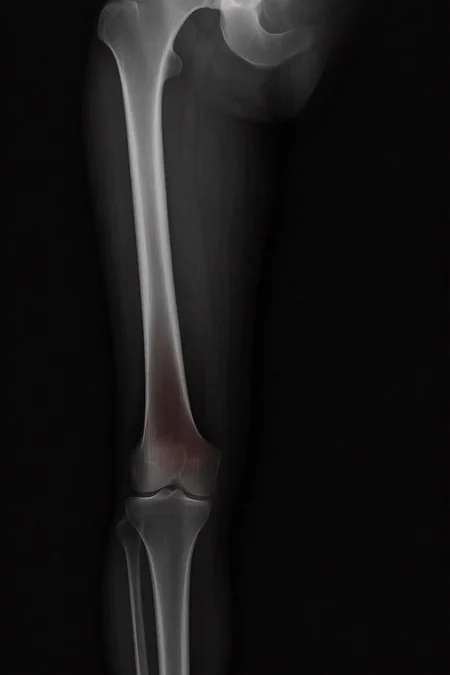

Can a model like Flux Kontext, designed for editing art and photography, be used to work with medical images, for example, with something 'as simple' as red-marking fractures?

The quick answer: it does do something interesting, but it over-scores and is far from reliable as a medical tool. It's a prototype to play with the idea, nothing more.

With a synthetic mini-dataset for Civitai of images made with 100% AI (10 healthy X-rays and 10 fractured):

False positives: 100% in healthy bones.

Fracture detection: ≈ 45%